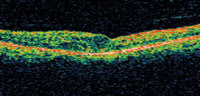

Rapidly emerging new technologies such as pharmacotherapy and expanded indications for vitreous surgery, alone or in combination with photocoagulation, offer promising new tools in the management of diabetic retinopathy and other retinovascular diseases.4, 5 Optical coherence tomography (OCT) now routinely employed in the diagnosis of macular disease often reveals edema, which is clinically undetectable. This creates both new dilemmas and opportunities for clinicians. Should we treat? If so, how? The current indications for photocoagulation of DME predate OCT technology and remain based on biomicroscopic findings.1 Thus, the risks of conventional photocoagulation do not currently justify treatment of DME based on OCT findings alone. However, the risk reduction offered by SDM suggests a possible role in the treatment of such early, as well as clinically significant, DME (Figure 4). As elsewhere in medicine, earlier intervention may improve patient outcomes. Tools such as SDM may improve our prospects of achieving the elusive ideal of "First, do no harm" while at the same time offering our patients effective treatment. Further investigation will determine the place of SDM in the management of diabetic retinopathy and other retinovascular disease.

| Figure 4. OCT of clinically significant diabetic macular edema prior to subthreshold diode micropulse photocoagulation (top) and 3 months postoperatively (bottom). |